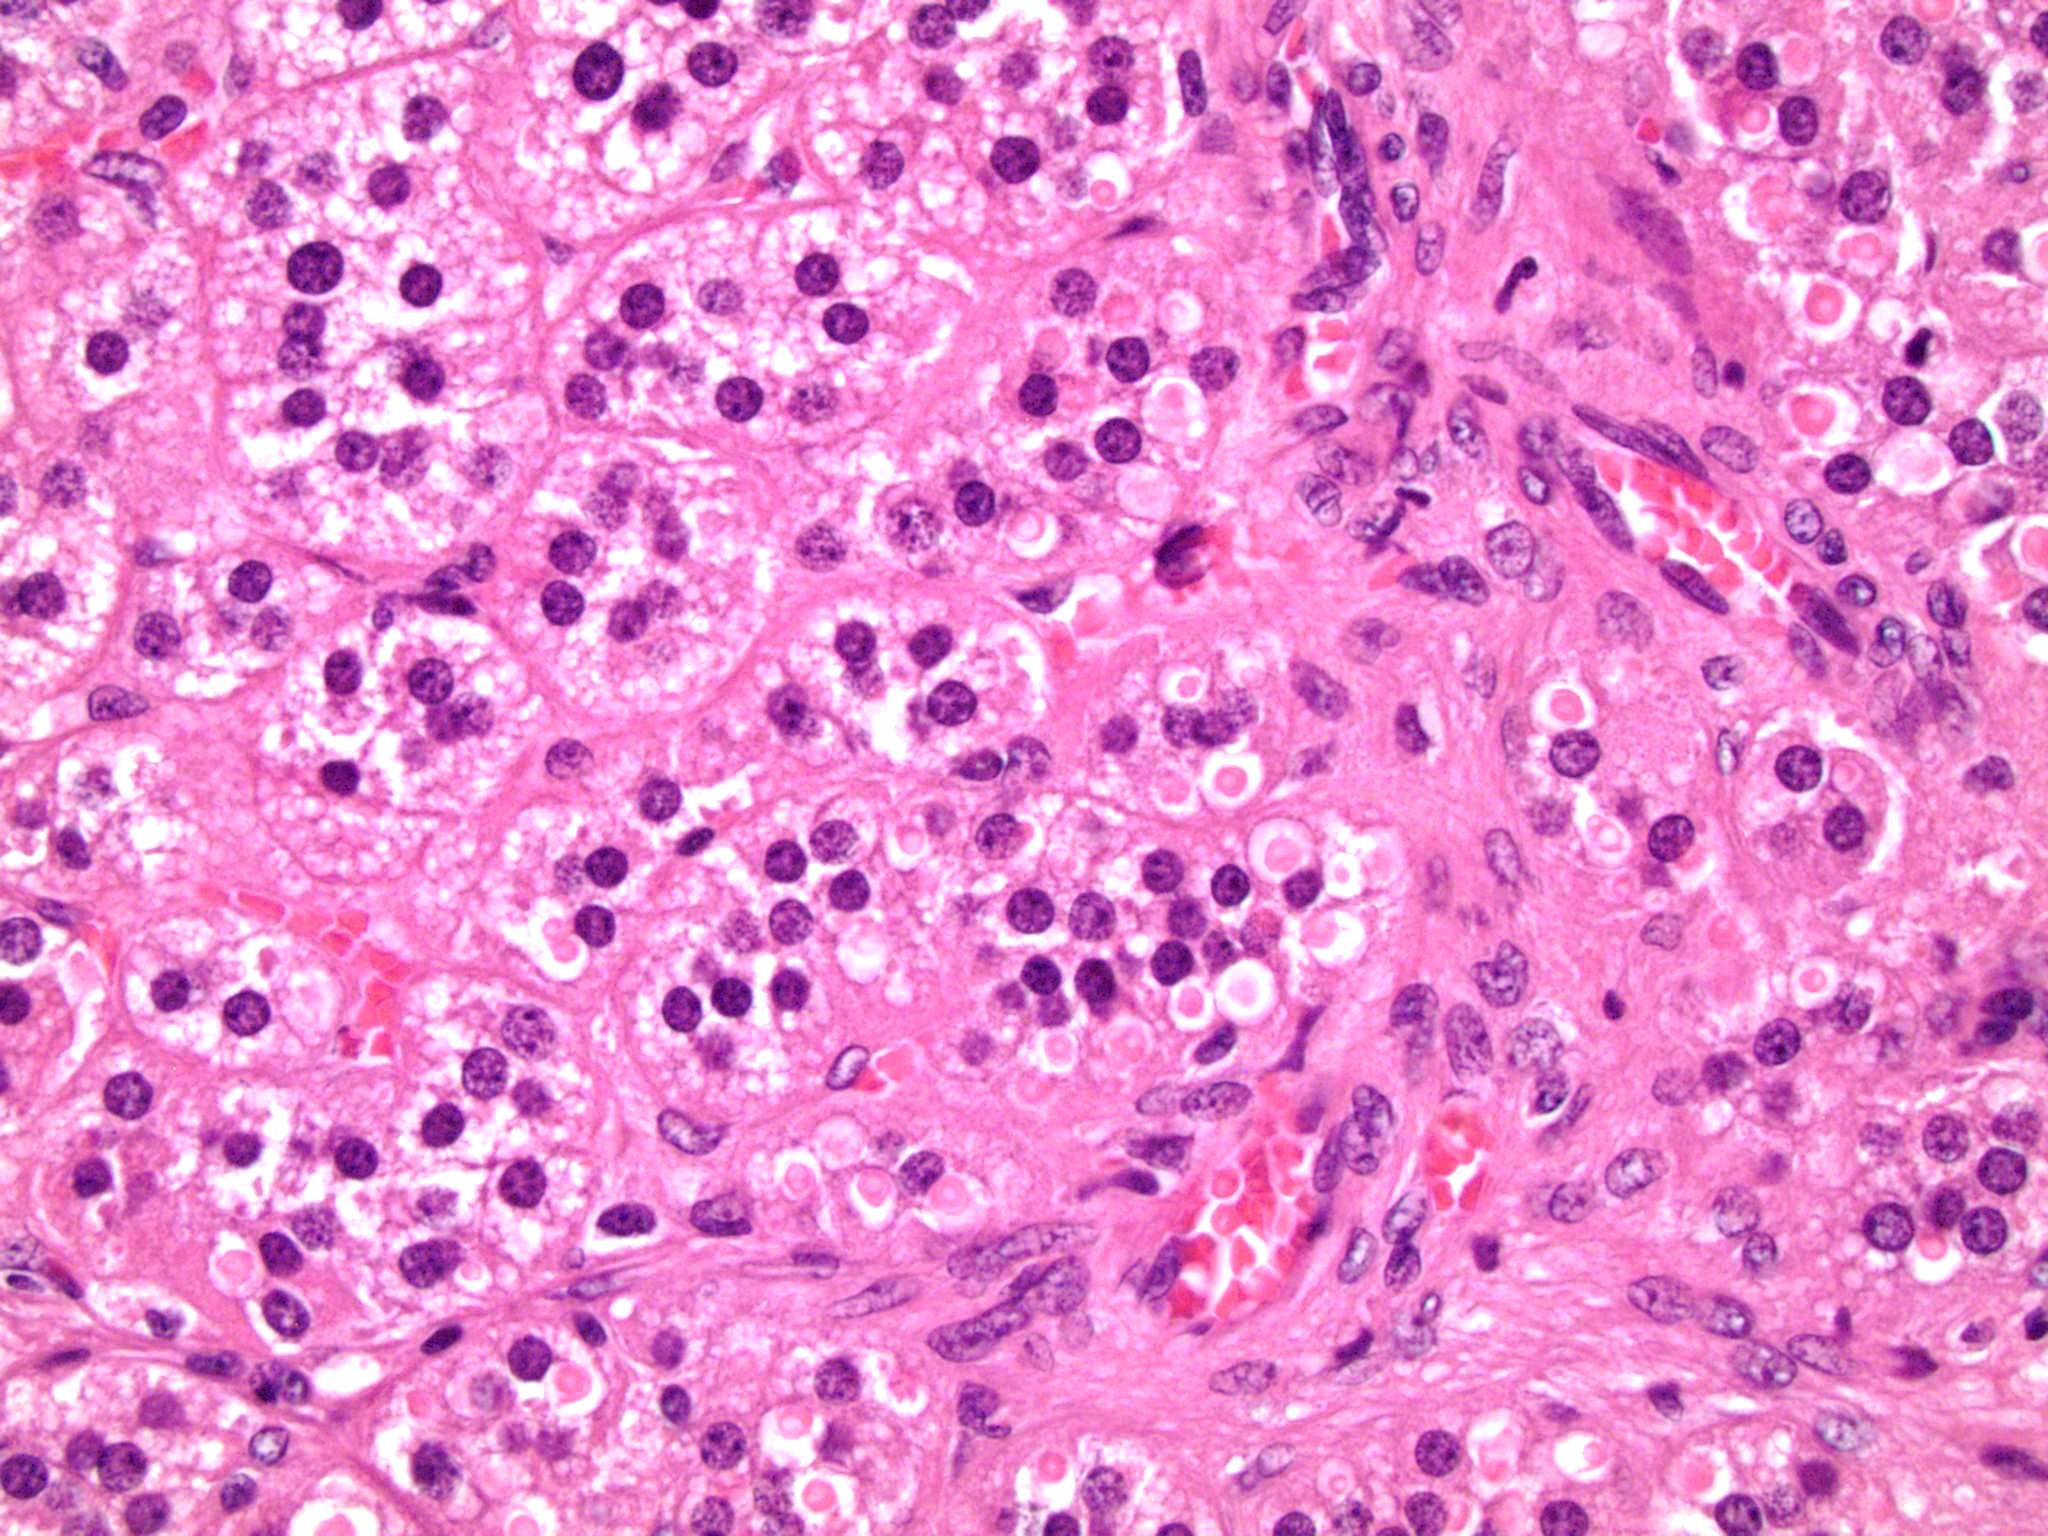

Microscopic (histologic) description

- In comparison to surrounding adrenal gland, adenoma cells are larger with different cytoplasm, increased variation in nuclear size

- Distinct cell borders, cells have abundant foamy cytoplasm reminiscent of zona fasciculata

- Balloon cells: clusters of cells with enlarged lipid-rich cytoplasm (seen in Cushing syndrome)

- Histologic variants: oncocytic, myxoid

Microscopic (histologic) images

Contributed by Xiaoyin "Sara" Jiang, M.D., Debra Zynger, M.D., @Andrew_Fltv on Twitter and @SueEPig on Twitter